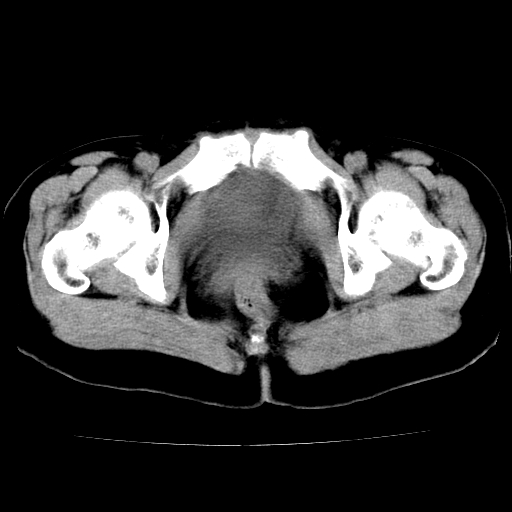

标题: CT24785:女,62岁,发现下腹部肿物半年。 [打印本页]

标题: CT24785:女,62岁,发现下腹部肿物半年。

女,62岁,发现下腹部肿物半年,下腹部不适。

考虑子宫平滑肌肉瘤可能性大。

实性成分太多,要是囊腺瘤也要考虑恶性。